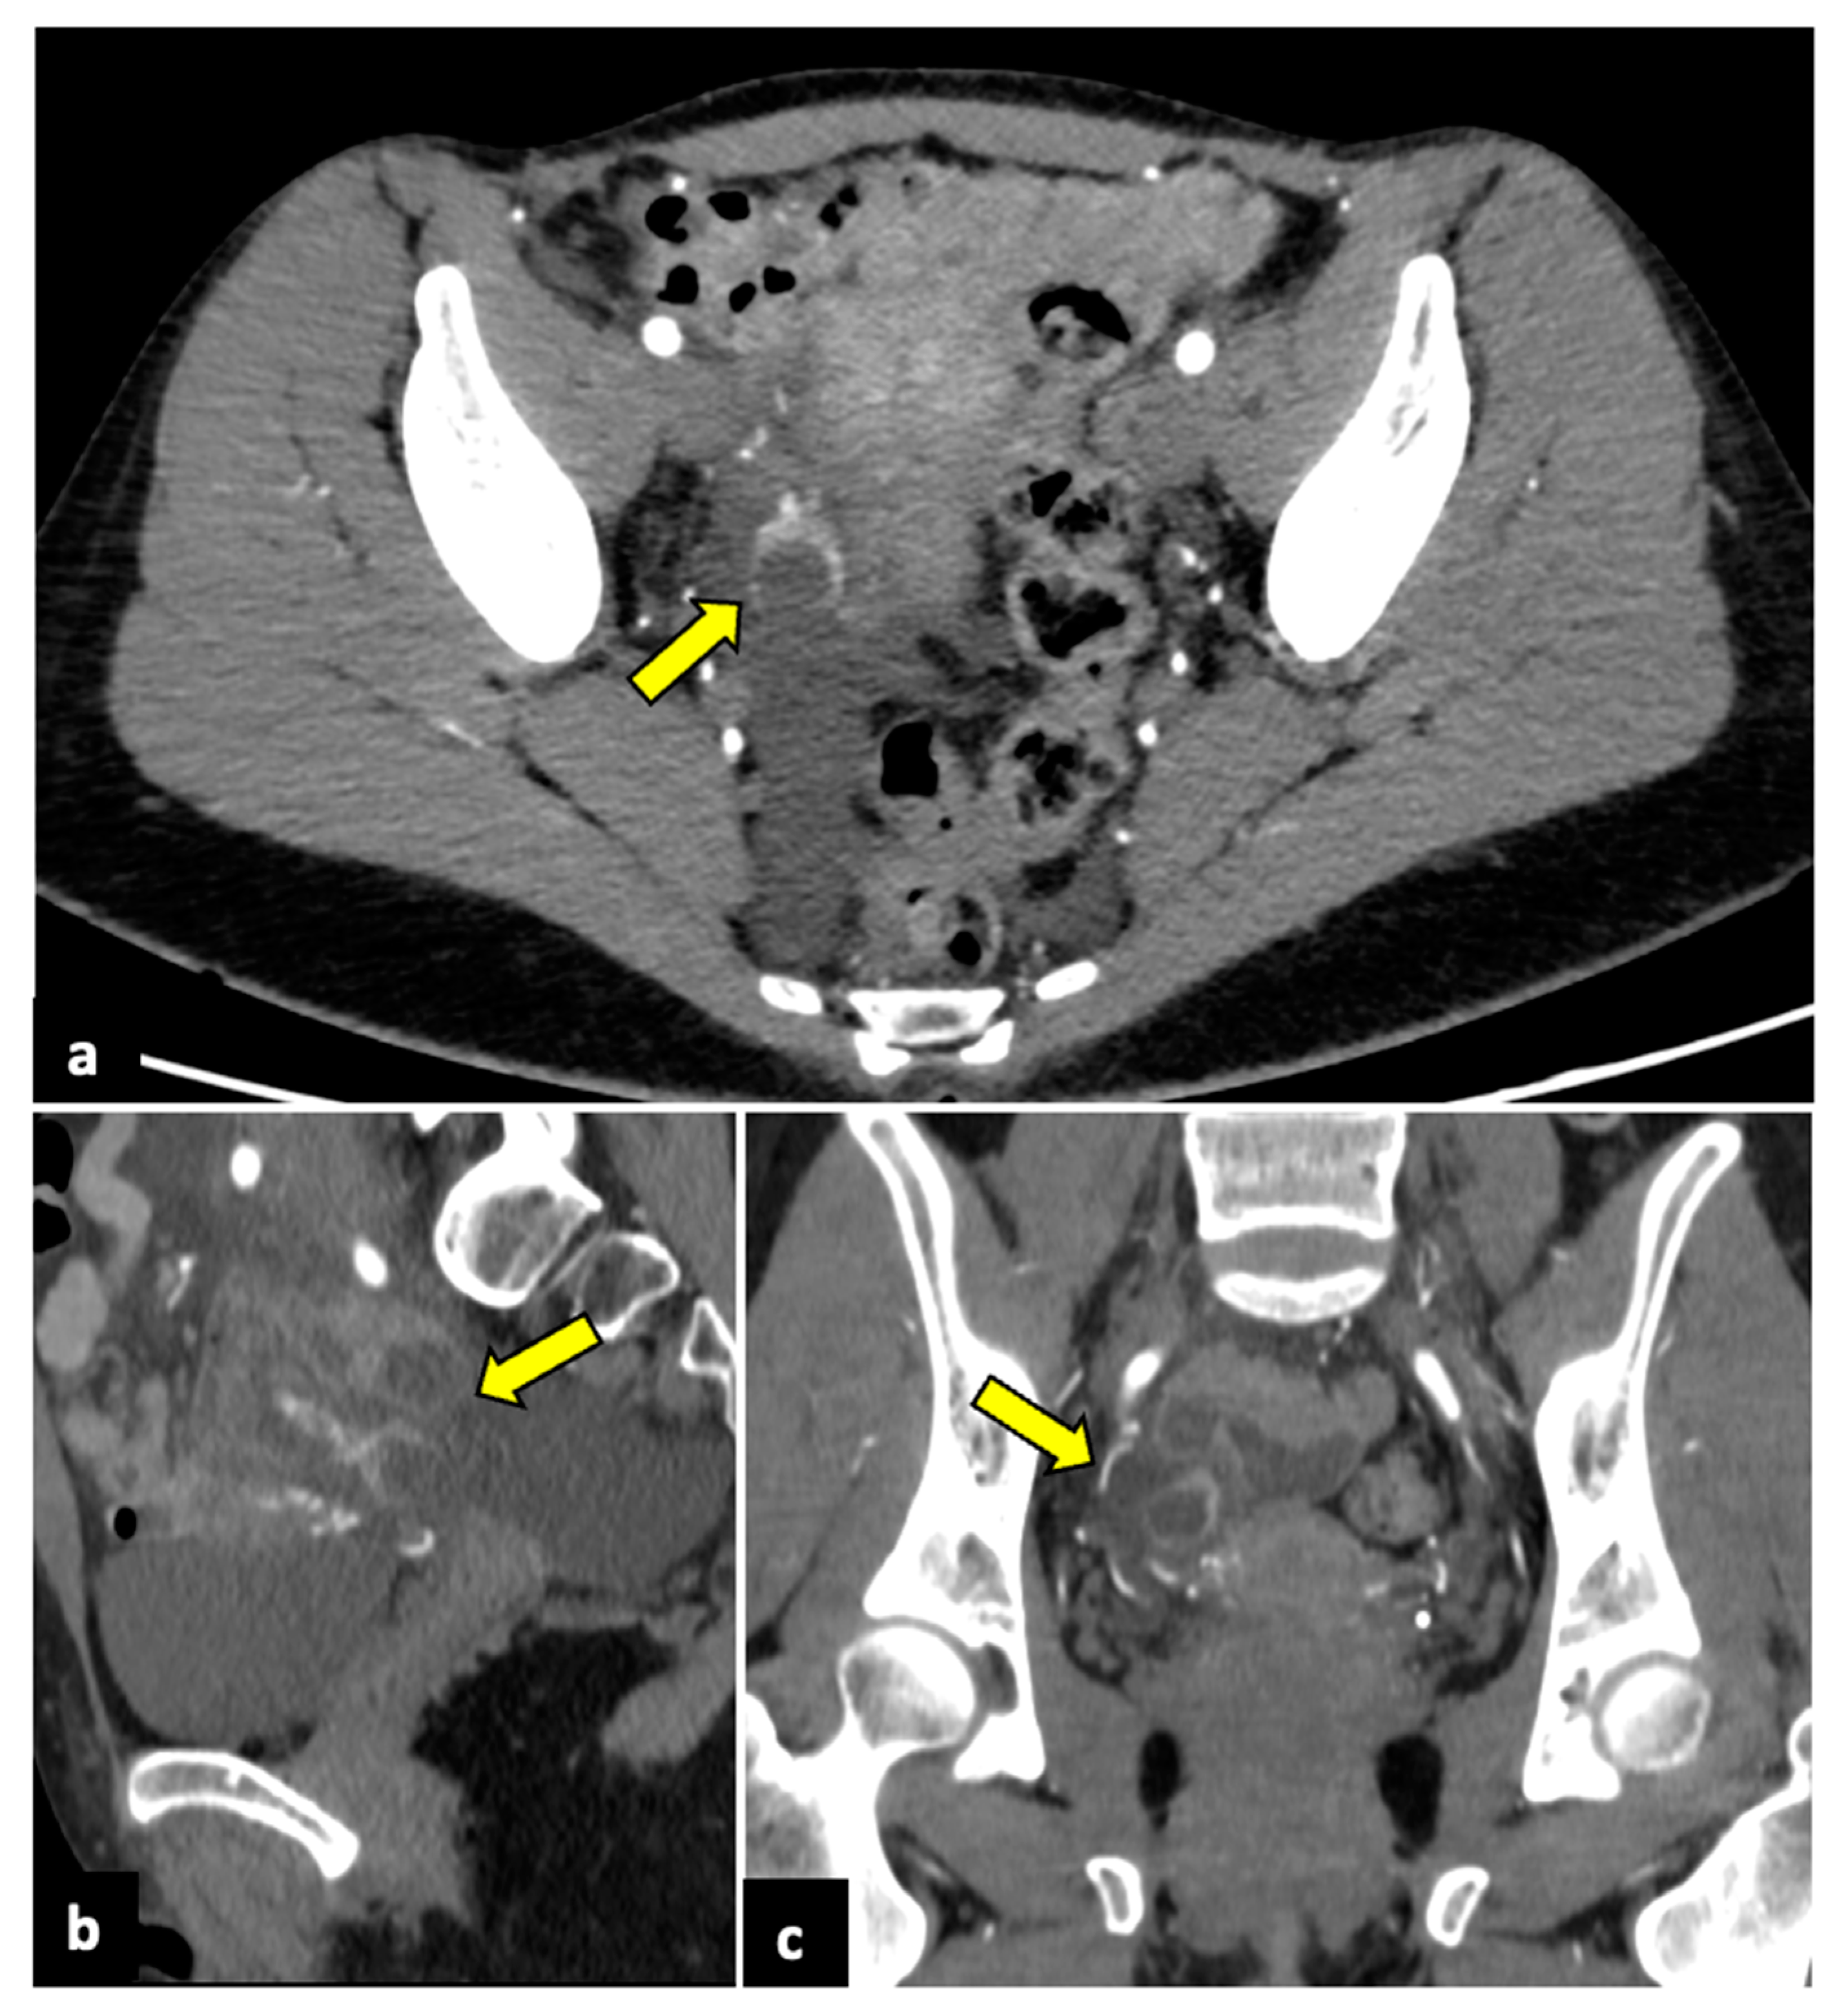

2.4. Complicated Uterine Leiomyomas

2.5. Endometriosis